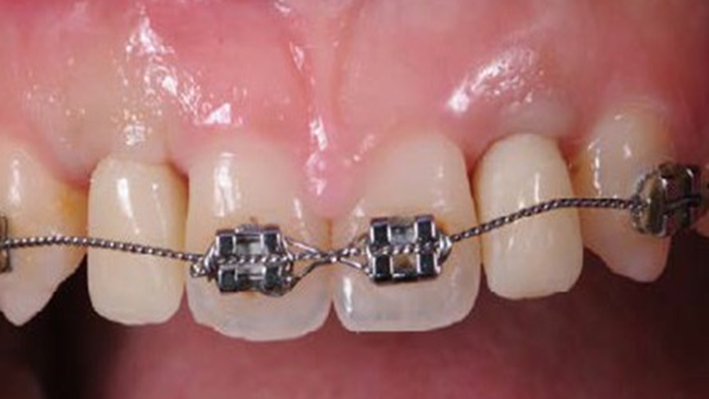

Clinical case: BPET PREDICTABILITY - State-of-the-Art SOCKET SHIELD

- Courtesy of Dr. Howard Gluckman, South Africa -

Socket Shield Technique, anterior esthetics, maxillary anterior, esthetic, esthetics, AnyRidge, Root Membrane Kit, Root Membrane Technique, Partial Extraction Therapy, PET, esthetic zone , Dr. Howard Gluckman

AnyRidge implant system, Root membrane kit, PET Kit